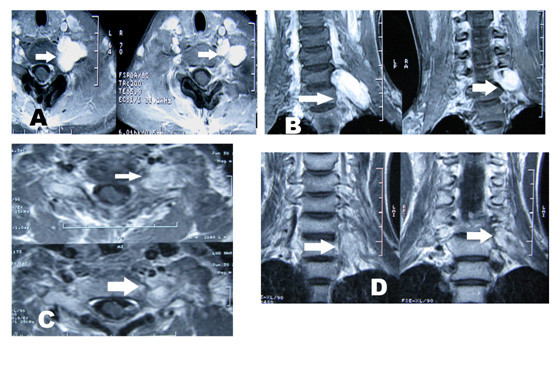

4、脊髓血管畸形、脊柱、椎管内和脊髓肿瘤的射波刀治疗: 脊髓血管畸形主要引起出血、盗血、脊髓压迫和静脉压增高症状,目前的主要治疗方法有介入治疗、显微外科治疗和介入-显微手术联合治疗。射波刀的出现为脊髓血管畸形提供了另一种治疗选择。Sinclair 等人最近报道了射波刀治疗15例脊髓血管畸形的初步结果。他们采用低分割照射(2~5次),经过2~5次的射波刀治疗,病灶周边的平均剂量为20.5Gy,平均随访时间为27个月。随访3年以上的患者中,脊髓血管畸形明显缩小,1例血管畸形经DSA证实完全消失。华山医院治疗1例颈段脊髓AVM,治疗后半年症状改善,治疗后1年走路跛行症状消失。椎管内脊髓外良性肿瘤也可选择射波刀治疗,但是当脊髓有受压症状时,最好选择手术治疗。椎管内小的多发神经纤维瘤是射波刀治疗的良好适应证,射波刀治疗后,多数肿瘤得到控制未再增大,1/3肿瘤缩小。椎管外的神经纤维瘤是射波刀治疗的良好适应症,治疗后肿瘤缩小(如图9所示)。脊髓内恶性肿瘤特别是一些转移瘤,除了引起脊髓受压症状外,还因神经根受刺激而产生疼痛症状;虽然常规放疗能在一定程度上起到控制肿瘤减轻疼痛的作用,但其治疗作用有限。射波刀的低分割照射对脊柱转移瘤和脊髓内转移瘤不仅可以起到控制肿瘤生长(或使肿瘤缩小),还可以明显减轻疼痛,改善患者的临床症状(如图10)。

图9:颈6-7椎管外神经鞘瘤(椎管内的肿瘤已经手术切除)射波刀治疗前后MRI。A: MRI水平位,箭头所指处为肿瘤;B: MRI冠状位,箭头所指处为肿瘤。C和D:射波刀治疗后半年,肿瘤缩小,强化减弱。